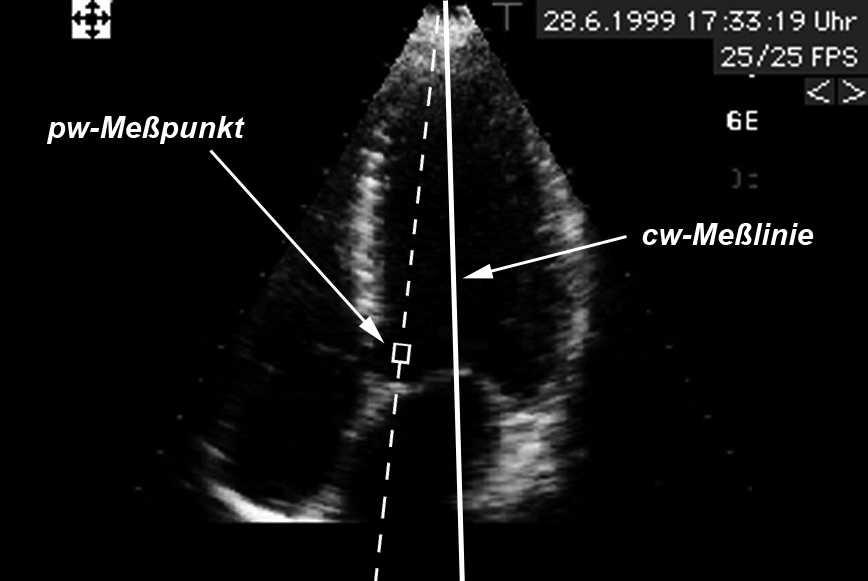

Ultraschallgeräte können nun in 2 unterschiedlichen Betriebsarten arbeiten: Als continous-wave-Doppler (cw-Doppler) und als pulsed-wave-Doppler (pw-Doppler):

Beim cw-Doppler arbeitet der Schallkopf gleichzeitig als Sender und Empfänger, d.h. ein Teil des Schallkopfes sendet kontinuierlich Ultraschallwellen aus und ein anderer Teil des Schallkopfes empfängt ebenso kontinuierlich den reflektierten Schall. Auf diese Weile erhält man die Doppler-Informationen sämtlicher Strukturen, die sich im Schallstrahl des Gerätes befinden. Wenn sich also beispielsweise 2 Blutgefäße kreuzen erhält man das gemischte Doppler-Signal aus beiden Gefäßen. Mit anderen Worten bedeutet dies, daß man mit Hilfe des cw-Dopplers nur Informationen über Flußrichtungen und die Flußgeschwindigkeiten bekommt, nicht aber Informationen über den Ort, an dem Flußrichtung und Geschwindigkeit gemessen wurden.

Bei pw-Doppler hingegen werden nur kurze Schallimpulse ausgesandt, die dann in den Körper eindringen und von den Blutkörperchen reflektiert werden. Indem man den Empfänger des Schallkopfes nur während bestimmter kurzer Zeiten einschaltet kann man erkennen, aus welcher Tiefe die Doppler-Information stammt, weil man die Ausbreitungsgeschwindigkeit des Schalls im menschlichen Körper kennt. Also:

Nun werden Sie sagen: Woher soll man denn wissen, in welcher Gewebetiefe welches Blutgefäß oder welche Klappe liegen? Ganz einfach: Man kombiniert beim Doppler-Echo die Doppler-Untersuchung mit einem „normalem“ Echo. In diesem normalen Echo kann man die in der Tiefe liegenden Strukturen (Gefäße, Herzklappen usw.) darstellen. In dieses „normale“ Echobild des Herzens werden dann diejenigen Stellen, an denen Doppler-Informationen gemessen werden sollen eingeblendet. Die Meßpunkte kann der Arzt an jede Stelle des Bildes schieben und somit gezielt an jeder beliebigen Stelle des Bildes seine Dopplermessungen vornehmen. Eine Variation der pw-Doppler-Untersuchung ist die Farbdoppler-Echokardiographie.

Der Vorteil einer solchen pw-Doppler-Messung ist im Gegensatz zum cw-Doppler also die Möglichkeit, auch die Orte zu bestimmen, an denen das Blut mit einer bestimmten Geschwindigkeit und Richtung fließt. Der Nachteil des pw-Dopplers besteht darin, daß man durch das kurze Sende- und Empfangsfenster nur relativ niedrige Blutgeschwindigkeiten messen kann (siehe „Ergebnisse“).